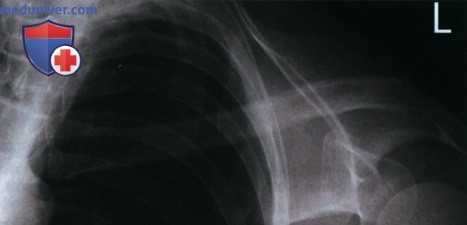

Рекомендации по анализу рентгенограмм (рис. 1):

РИСУНОК 1 Рентгенограмма ключицы в ПЗ проекции: правильное положение.

• Медиальный конец ключицы находится вблизи латерального края позвоночного столба (рис. 3 и 4)

• Ключица и верхний угол лопатки визуализируются на одном поперечном уровне (рис. 5 и 6)

РИСУНОК 3 Рентгенограмма ключицы в ПЗ проекции. Пациент повернут в противоположную сторону от исследуемой ключицы. РИСУНОК 4 Рентгенограмма ключицы в ПЗ проекции. Пациент повернут в сторону исследуемой ключицы. РИСУНОК 5 Рентгенограмма ключицы в ПЗ проекции. Верх срединной коронарной плоскости наклонен вперед. РИСУНОК 6 Рентгенограмма ключицы в ПЗ проекции. Верх срединной коронарной плоскости наклонен назад.

а) Поворот туловища в противоположную сторону от исследуемой ключицы. На рентгенограмме ключицы в ПЗ проекции выявить ее ротацию и продольное проекционное укорочение можно, сравнив положение медиального конца ключицы и позвоночного столба. Если туловище отвернуто от исследуемой ключицы, то ее медиальный конец будет накладываться на позвоночный столб (рис. 3).

б) Поворот туловища в сторону исследуемой ключицы. Если при рентгенографии ключицы в ПЗ проекции туловище повернуто к исследуемой ключице, на рентгенограмме медиальный конец ключицы будет отодвинут от позвоночного столба, а сама она будет подвергаться продольному проекционному укорочению (рис. 4).

в) Наклон верха срединной коронарной плоскости вперед. Если при рентгенографии ключицы в ПЗ проекции верх срединной коронарной плоскости наклонен вперед, на рентгенограмме верхний угол лопатки будет визуализироваться выше ключицы (рис. 4).

г) Наклон верха срединной коронарной плоскости назад. Если при рентгенографии ключицы в ПЗ проекции верх срединной коронарной плоскости наклонен назад, на рентгенограмме верхний угол лопатки будет визуализироваться ниже ключицы (рис. 5).

Пример анализа рентгенограмм ключицы в ПЗ проекции

1. Анализ. Медиальный конец ключицы отодвинут от латерального края позвоночного столба. Туловище было повернуто в сторону исследуемого плечевого сустава.

2. Коррекция. Поверните туловище в противоположную сторону так, чтобы плечевые суставы располагались на равном расстоянии от ПИ.

1. Анализ. Верхний угол лопатки проецируется выше середины ключицы. Верх срединной коронарной плоскости был наклонен вперед.

2. Коррекция. Выпрямите верхнегрудной отдел позвоночника так, чтобы срединная коронарная плоскость располагалась параллельно ПИ.

1. Анализ. Верхний угол лопатки проецируется ниже середины ключицы. Верх срединной коронарной плоскости был наклонен назад. Медиальный конец ключицы не входит в экспозиционное поле. ЦЛ был направлен издишне латерально.

2. Коррекция. Выпрямите верхнегрудной отдел позвоночника так, чтобы срединная коронарная плоскость располагалась параллельно ПИ. Направьте ЦЛ медиальнее приблизительно на 2,5 см. Отколлимируйте экспозиционное поле так, чтобы в него вошел медиальный конец ключицы.